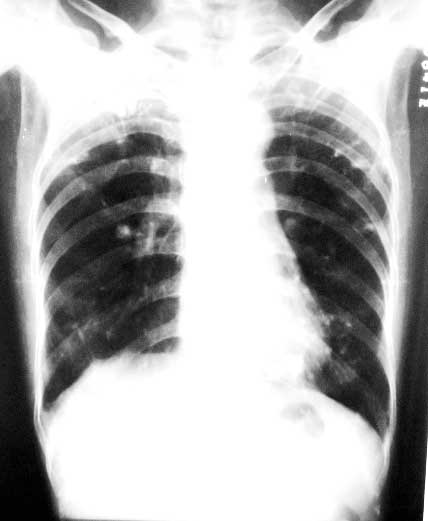

标题: X0226:[原创]两肺结节状高密度

f/63y,胸痛数天,曾患结核性胸膜炎。

陈旧性肺结核

1、双上中继发性肺结核,右侧胸膜粘连;

双上肺结节条索。点仗钙化。透光度增强,诊断肺结核,肺气肿

双上肺陈旧性结核,右侧胸膜粘连,肺气肿右侧肺门可能是伪影

两肺钙化灶,两上胸膜增厚、粘连

意见:1陈旧性肺结核;2右侧胸膜粘连;3两中下肺气肿。